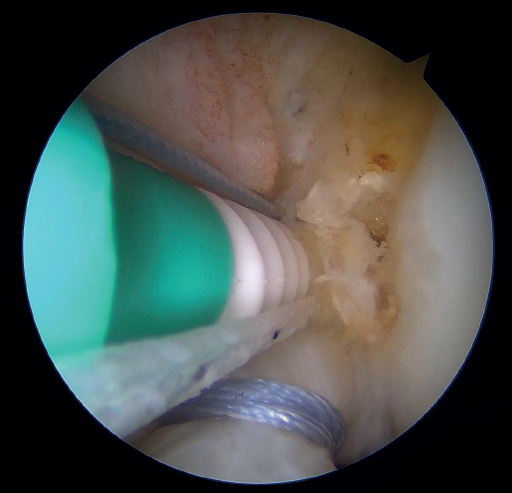

Outside the knee, the threads are loaded into a knotless anchor implant with a tape that will act as anterior reinforcement of the ACL when attached to the tibia. Once the implant has been loaded, it is inserted into the previously prepared site. This step is facilitated when viewing is made from the anteromedial portal, as it affords a better perspective of the zone (Figure 5). Once the implant has been inserted, the suture threads are cut at the level of the condylar wall.

With vision through the anterolateral portal, the tibial guide of the ACL is placed in the central zone of its distal insertion, and a tunnel is made with a 2.4 mm cannulated drill through which a loop-ended nitinol is passed and retrieved through the accessory anteromedial portal. The nitinol serves as a retriever, to load the tape through it and pass it through the tibial tunnel. Once the tape is retrieved, it is secured to the tibial cortex with a knotless anchor implant or button, tightening the tape with the knee in near full extension. If a threaded implant is used, it is important to check that no implant threads protrude at the cortex, as this could cause discomfort in the future.

Under arthroscopic vision, it is important to confirm tension of the ACL both in the full range of motion and with the use of a palpator and the Lachman and anterior drawer maneuvers (Figure 6).